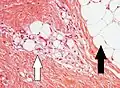

Lipoblasts are seen in liposarcoma[7] and characteristically have abundant multivacuolated clear cytoplasm and a dark staining (hyperchromatic), indented nucleus.